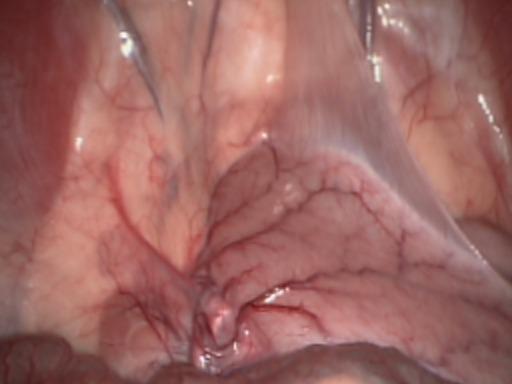

Validation in real endoscopies. We used the Hamlyn dataset [30], that contains intracorporeal endoscopic RGB scenes with weak textures, deformations and reflections. Specifically, we chose scenes 1 and 17 (see Figure LABEL:fig:hamlyn), which are significant exploratory ones. Most of Hamlyn’s videos have very small camera motions, being of no interest for benchmarking odometry methods. We slightly cropped the images to remove black pixels at the borders. Depth data was taken from the public tracking test data of EDaM [9] which was estimated by a single-view dense depth network trained in a self-supervised manner in all Hamlyn scenes except for the test ones. Note that this depth does not have the same quality as the real ground truth one from the Drunkard’s Dataset.

Refer to caption

(a) Scene 1 frame

(b) Scene 17 frame

(e) APTEksubscriptAPTE𝑘\mathrm{APTE}_{k} plots in Hamlyn’s scene 1.

[Uncaptioned image]

(f) APTEksubscriptAPTE𝑘\mathrm{APTE}_{k} plots in Hamlyn’s scene 17.

Figure 4: Camera tracking performance on the Hamlyn dataset. APTEksubscriptAPTE𝑘\mathrm{APTE}_{k} values along the N𝑁N different k𝑘k-frames-length-loops in Hamlyn’s scenes 1 (a) and 17 (b) for EDaM [9], DROID-SLAM [34] and Drunkard’s Odometry (ours) with and without having been trained in deformable scenes of the Drunkard’s Dataset (i.e. trained in level 1 and 0, respectively). The training on deforming scene substantially improves the performance of our method.